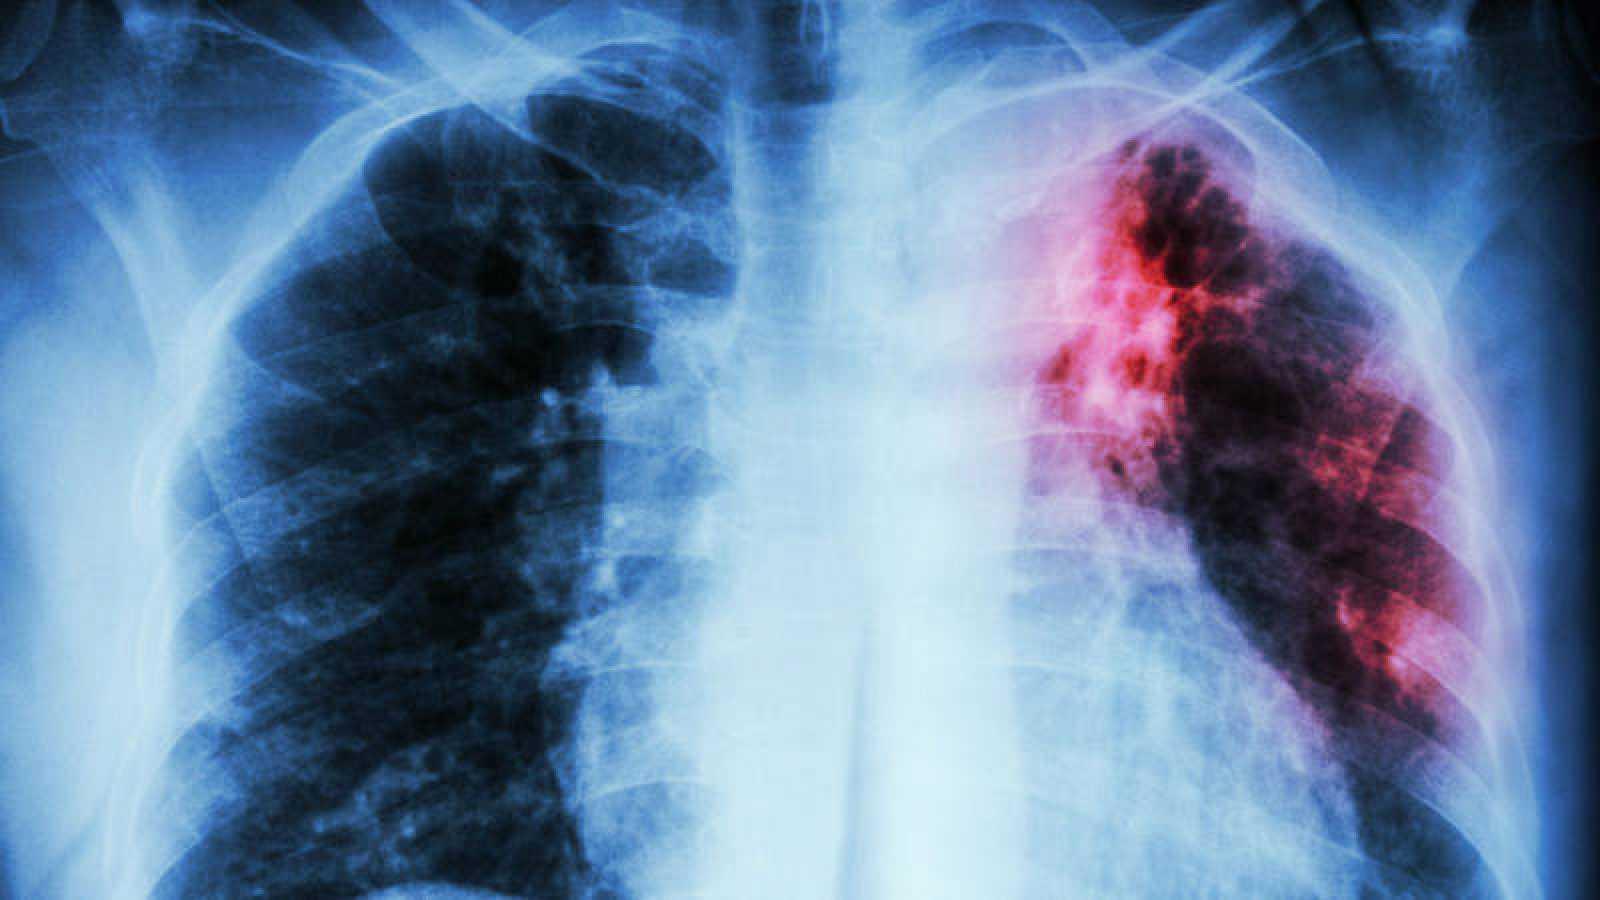

El Ministerio de Salud reportó que hay dos médicos residentes del hospital Santo Tomás afectados con tuberculosis. Se encuentran incapacitados y su condición de salud es estable.

El Minsa hace un llamado de atención a la ciudadanía que ante la dificultad para respiratoria, dolor en el pecho, tos por más de 15 días, sudoración excesiva, fiebre, fatiga, y expulsión de flema con sangre, debe acudir de inmediato al médico, porque podría tratarse de tuberculosis.

En lo que va del año 2019, el programa encargado de este enfermedad registra 1,450 casos de tuberculosis a nivel nacional y las regiones con mayor incidencia de casos son la provincia de Bocas del Toro, Guna Yala y Panamá Este, por lo que se mantiene el control y vigilancia.